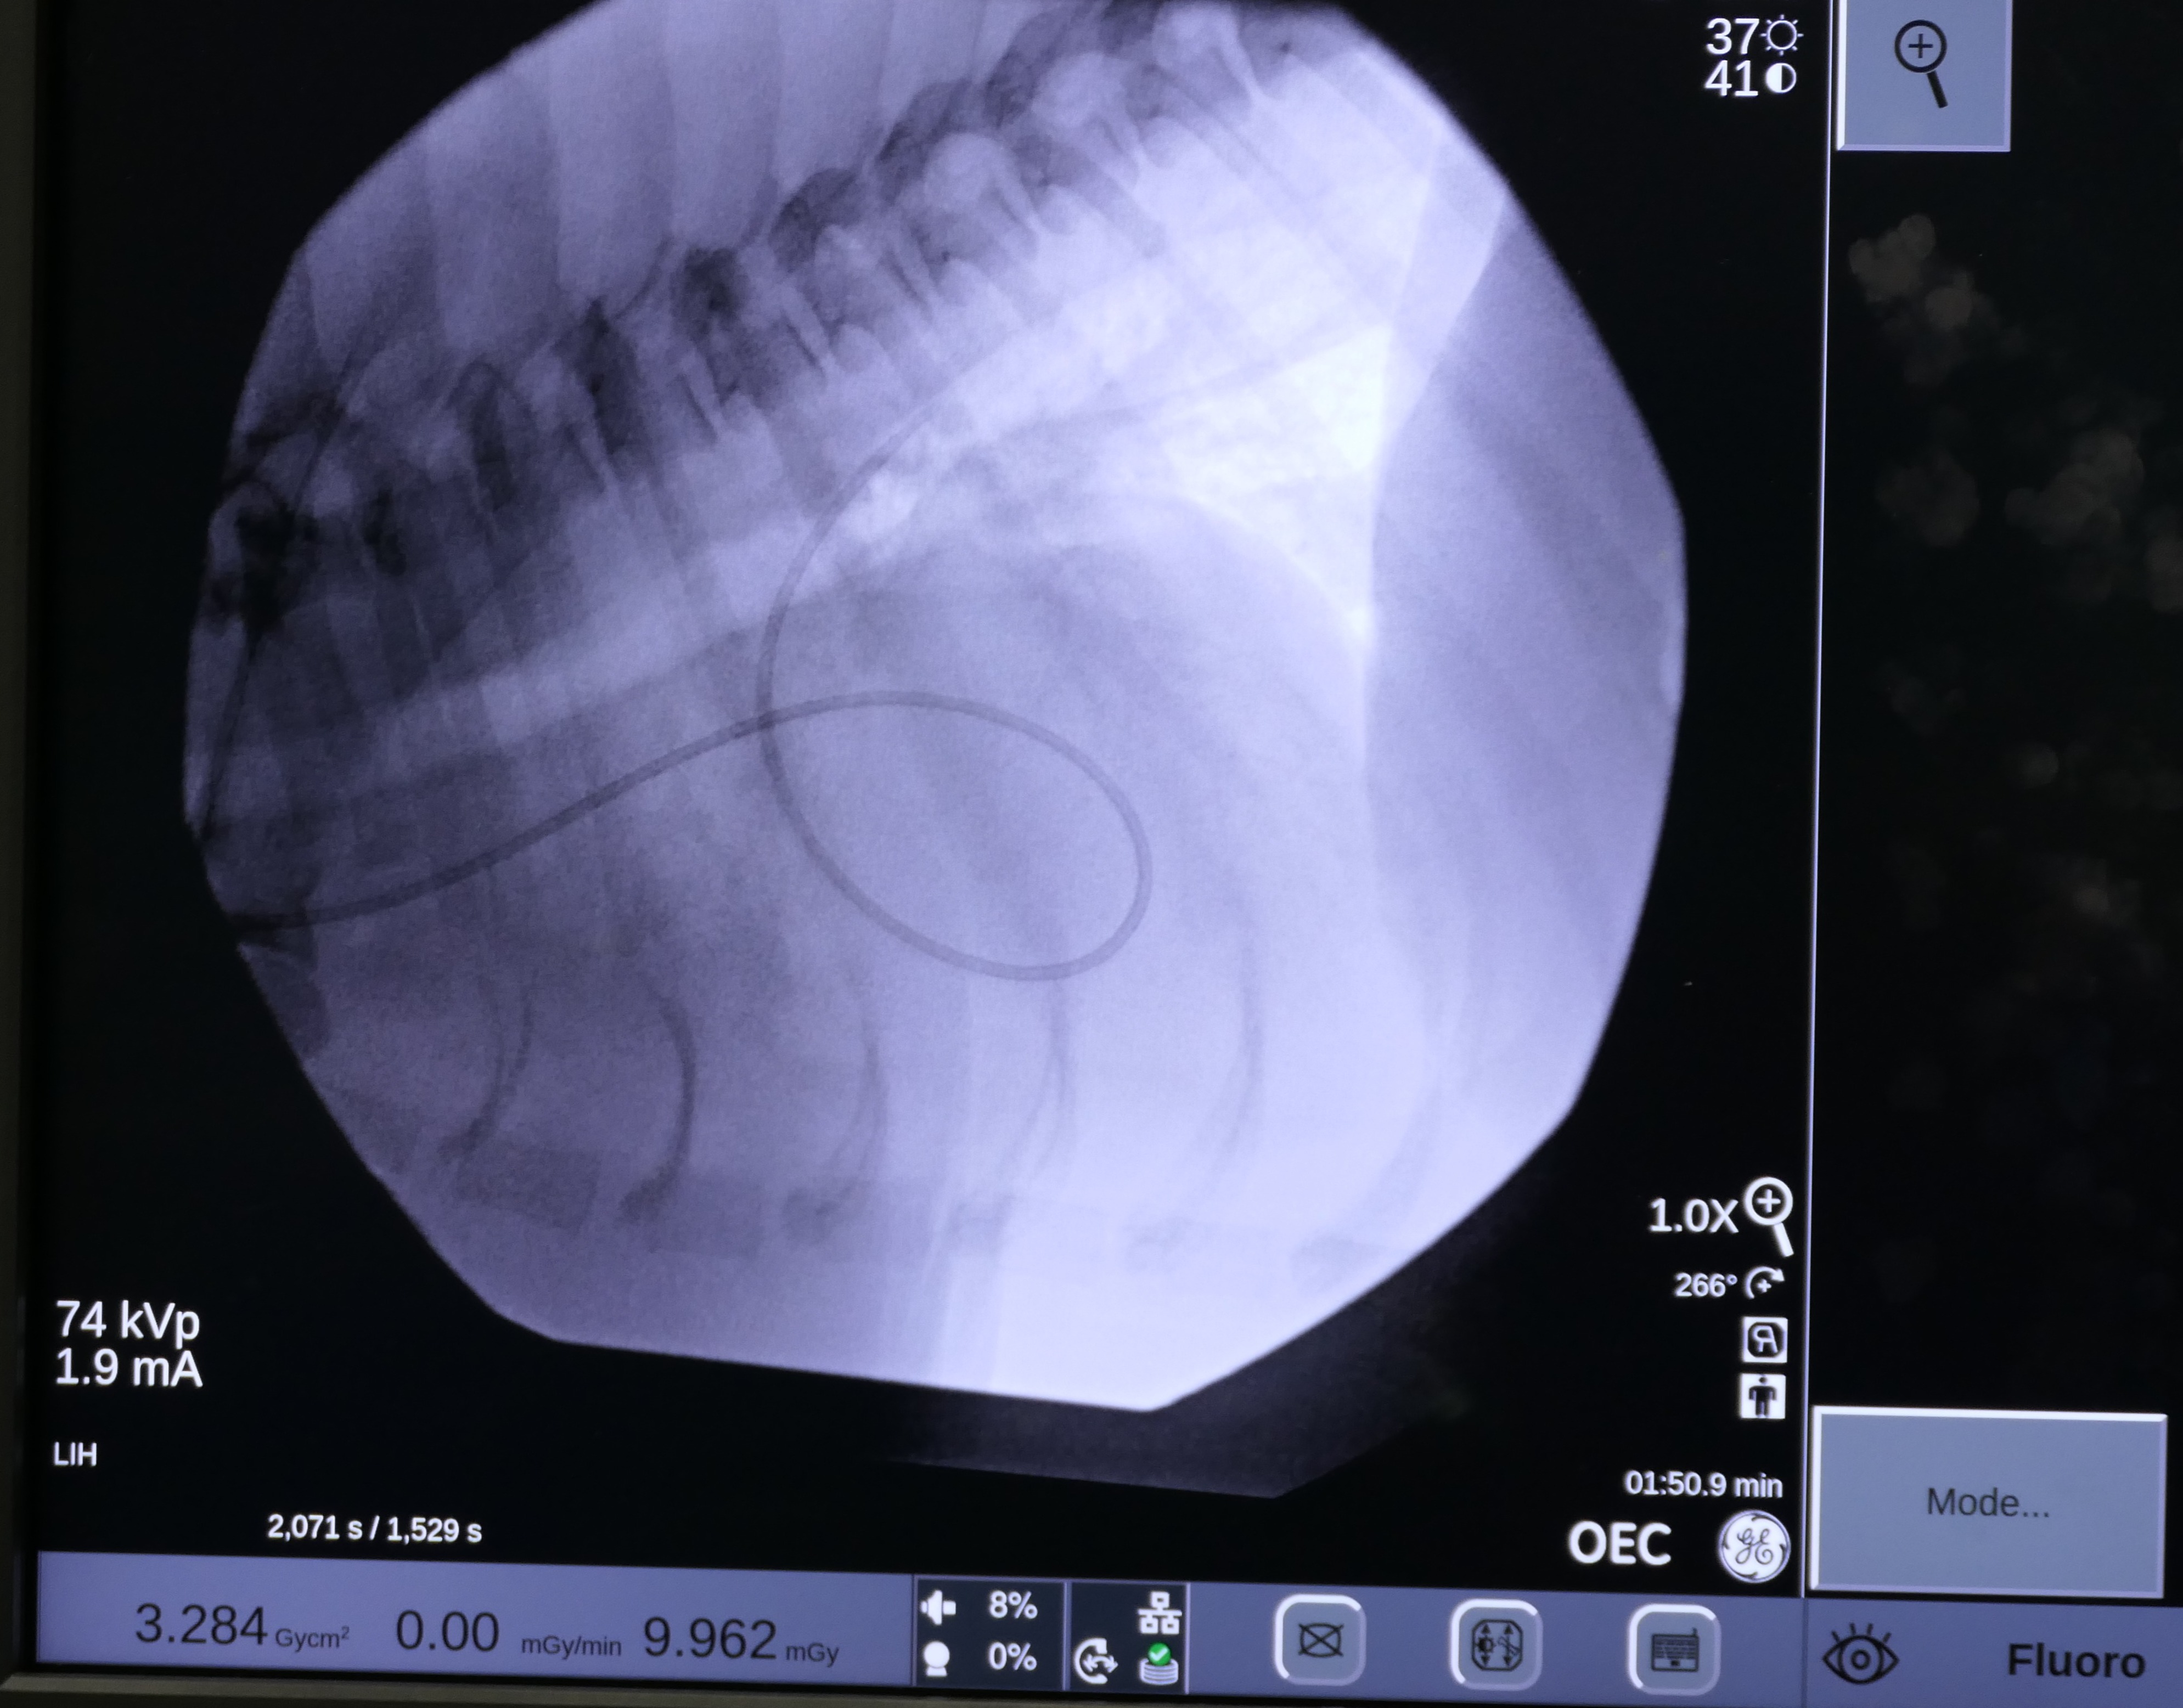

On May 7 2024, Snoop underwent a balloon valvuloplasty at MVRH. The procedure involved placing Snoop under general anesthesia and accessing the affected valve via the external right jugular vein. In order to gain access to the heart, a vascular introducer is first placed into the vein. This allows exchanging various wires and catheters without causing blood loss. Then, using fluoroscopy (Live X-rays) a catheter is advanced into the heart. This catheter has a small air balloon in its tip working as a “sail” and flowing downstream into the heart. Once the anatomy is assessed by using contrast, a Guire is placed to be used as a roadmap. Over this wire, a catheter with a large balloon in its tip is positioned across the fused valves. Once the balloon is inflated, the high pressures reached with this balloon separate the valve leaflets, decreasing the obstruction. This balloon reaches up to 18 atmospheres of pressure, and to put this in perspective, it is the equivalent of roughly stretching it with 260 pounds of force.